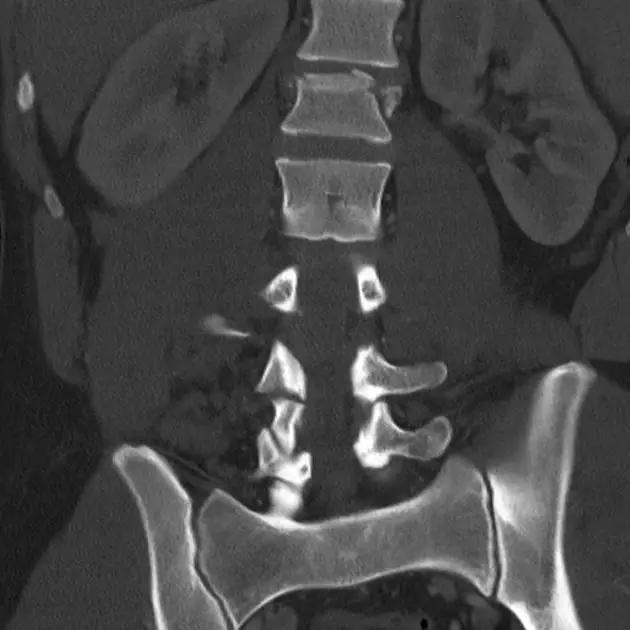

3. Chance 骨折

胸腰段椎体的分离性骨折,伴随脊髓、神经根、椎体的水平方向的崩裂骨折。又称座带骨折(seatbelt fracture)。

由 Chance 于 1948 年首先描述此骨折,故文献又常称 Chance 骨折,为一种屈曲拉伸骨折。典型的损伤机制为汽车座带束于患者腰腹部,当高速行驶的汽车突然减速或撞车时,座带支点以上的躯干屈曲,前冲力还同时产生一个向前拉伸的力量。将椎体由后方向前撕裂,骨折线横过椎体、椎弓根和椎板,椎体后部的韧带完全撕裂。有时前纵韧带亦可撕裂,常合并有神经系统的症状。

(来源:Radiopaedia)